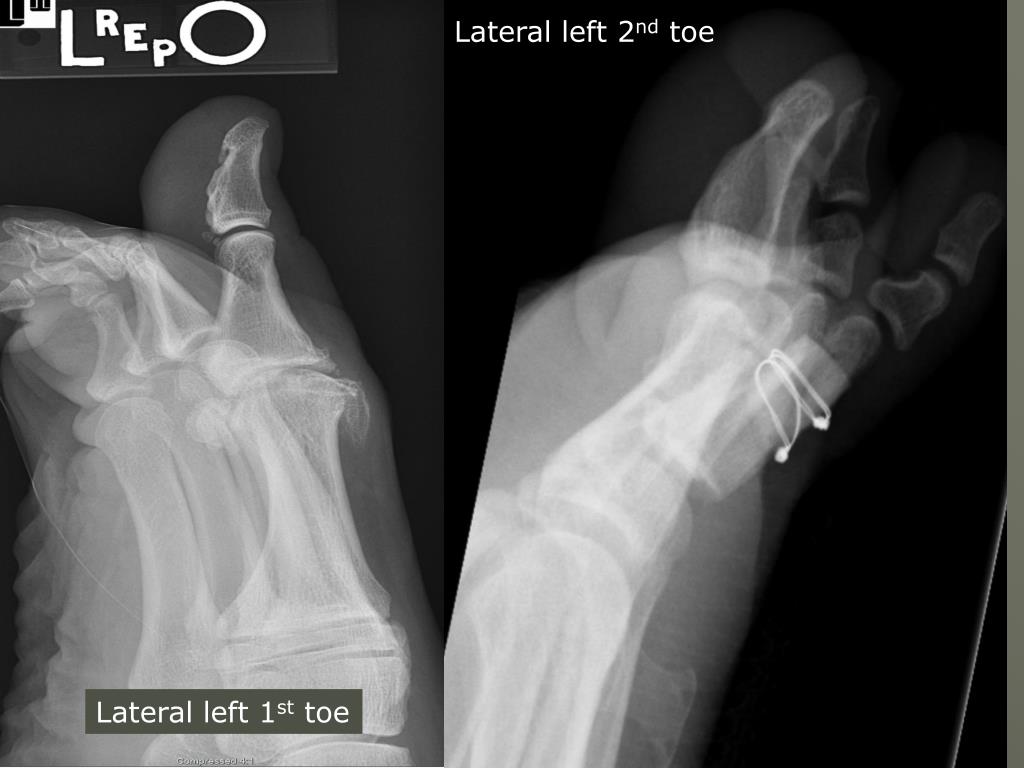

12. Lateral toes Lateral left 3rd toe Lateral left 2nd toe lateromedial Mediolateral • Do lateromedial (1st-3rd) and mediolateral (3rd-5th) to get the toe closest to the film

14. Lateral left 2nd toe Lateral left 1st toe